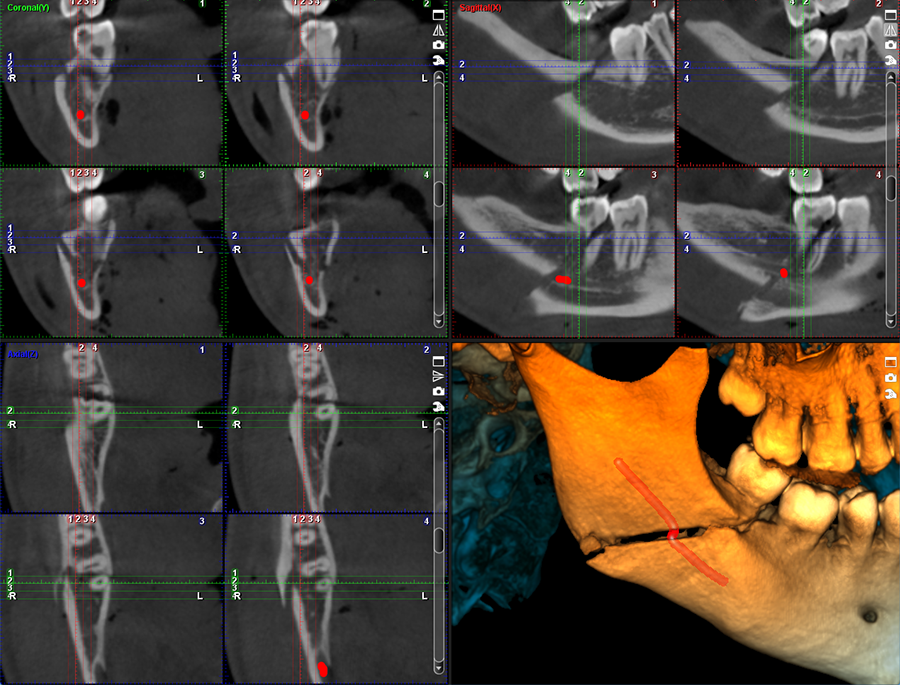

Ustawienia wstępne dla obrazowania TMJ

Planmeca ProMax 3D Mid jest nie tylko doskonałym wyborem w przypadku obrazowania stomatologicznego, ale również świetnie sprawdza się w przypadku pełnego obrazowania twarzowo-szczękowego. Unit posiada wiele ustawień wstępnych dla poszczególnych obszarów anatomicznych opracowanych specjalnie z myślą o obrazowania uszu, nosa i gardła.

Obrazy Kliniczne Planmeca ProMax 3D Mid